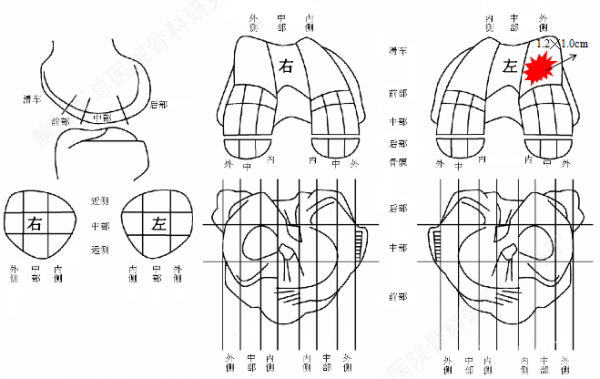

缺损部位的标记:根据关节镜下的检查评估来确定损伤部位,范围,以决定二次手术的切口部位。

软骨组织的获取:关节镜下观察关节软骨的股骨髁间非负重区的穹窿部位或股骨滑车区边缘非负重部位,清理周围的滑膜组织,应用髓核钳或鹅眉凿获取患者关节软骨100-200mg。